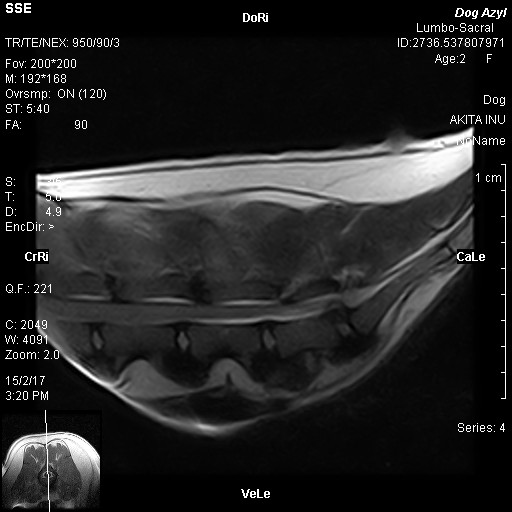

Akira, narodená cca február 2009, sa našla pri Lehniciach. V tejto lokalite je to už za posledný pol rok asi piata akita, takže je evidentné, že sa ich nejaký množiteľ zbavuje! Akira je dokonalou predstaviteľkou plemena americká akita. Má za sebou neľahké obdobie, prešla to totiž operáciou vyskočenej platničky, ktorej predchádzal život v krutých bolestiach :( Platnička je opäť na mieste, ale Akira má problém s celou chrbticou, ktorá je zrastená (prikladáme RTG snímky). Akira sa teda bude musieť doživotne šetriť, aby nemala zbytočné bolesti. To znamená kontrolovaný pohyb, určite nenechávať niekde na dvore bez dozoru, aby celý deň lietala! Prechádzky iba na vodítku, kľudne na dlhom, ale treba dať pozor aby nezabehla a nezačala sa hrať na naháňačku. Skákanie minimalizovať ako sa len bude dať, a ideálne žiadne schody! Akira si túto starostlivosť ale veľmi zaslúži :) Je to neopísateľný miláčik, lásky má na rozdávanie aj za troch. Miluje ľudí, úplne každého človeka zbožňuje, aj toho, ktorého ešte nepozná :) Na klinike si ju celý personál zamiloval a ona sa túlila ku každému. Akiru nám dokonale opísal pán doktor na klinike, ktorý povedal, že "je to miláčik, ale jadrový fyzik to nie je" :D Toto Akiru dokonale vystihuje ale to samozrejme neznamená, že sa nič nedokáže naučiť, len z nej nikdy nebude komisár Rex a ani Hatchiko :D Je to také milé trdielko, ktoré nechce nič iné, ako milovať a byť milovaná. Je nenáročná, nekonfliktná, znášanlivá so psíkmi aj fenkami, jednoducho dokonalá. Hľadá si rodinu, ktorá jej bude vedieť zabezpečiť potrebnú opateru a starostlivosť. Samozrejme konzultácia novej rodiny s ortopédom je možná. Akira čaká na svoju druhú šancu od februára 2017.

Akira, geboren ca. im Februar 2009, wurde in Lehnice gefunden. In dieser Umgebung ist das schon fünfte Akita in den letzten 6 Monaten, also offensichtlich werden die von ein Vehrmehrer rausgeschmissen. Akira ist typischer Darsteller von Amerikanische Akita. Sie hat schwere Zeiten hinter sich. Sie hat große Schmerzen im Rücken gehabt, ihre Bandscheibe wurde operiert. Bandwechsel ist wieder auf seinem Platz, aber Akira hat Problem mit dem ganzen Rückgrat (die RTG Bilder legen wir bei). Akira muss sich den Rest des Lebens schonen, damit sie keine unnötigen Schmerzen hat. Das heißt die Bewegung unter Kontrolle zu halten, kein freies Laufen am Hof ohne Aufsicht. Die Spaziergänge nur an der Leine, auch auf längeren, nur man muss aufpassen dass sie nicht laufen will. Springen muss so viel es geht minimalisiert, ideal keine Treppen. Akira verdient sich diese Sorgfalt :) Sie ist ein unbeschreibliches Liebling, Liebe kann sie für drei verschenken. Sie liebt sehr alle Menschen, sogar auch Fremde :) In der Klinik hat sie das ganze Personal geliebt. Akira wurde von Hr. Doktor so beschrieben: „sie ist ein Liebling, kein Kernphysiker“ Das heißt aber nicht, dass sie nichts lernen kann, aus ihr wird nur kein Kommissar Rex und kein Hatchiko werden. Sie ist so lieb und das einzige was sie will ist geliebt zu werden und jemanden zu lieben. Sie ist nicht anspruchsvoll, konfliktlos, erträgt sich mit anderen Hunden, einfach vollkommen! Sie sucht eine Familie die ihr die notwendige Versorgung geben kann. Selbstverständlich sind weitere Konsultationen mit einem Orthopäden möglich. Akira wartet auf ihre zweite Chance seit Februar 2017.